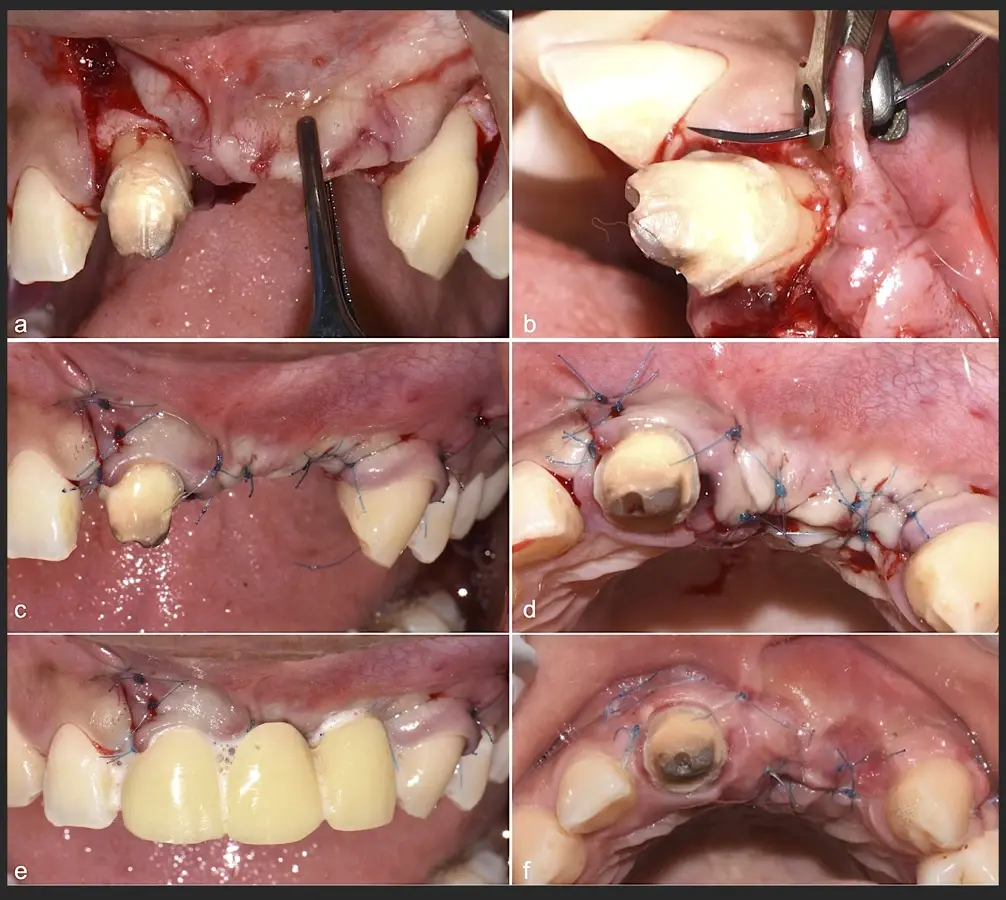

Paciente de sexo femenino de 36 años de edad, llega a la consulta por presentar una restauración protésica inadecuada. En el examen clínico se observa una restauración protésica provisional acrílica sobre las piezas 1.1 y 2.2. Adicionalmente, se aprecia recesión gingival a nivel de la pieza 2.2 y deficiencia horizontal severa de reborde a nivel de la zona edéntula correspondiente a la pieza 2.1. En la evaluación tomográfica se observa ausencia total de tabla ósea vestibular en la pieza 2.2, y se corrobora el déficit en la zona edéntula de la pieza 2.1, para lo cual se indica una reconstrucción de estructuras óseas con hueso en bloque de origen bovino y posteriormente la colocación de implantes dentales.

Figura 34. Vista frontal donde se observa deficiencia vertical del reborde óseo a nivel de las piezas 2.1, 2.2.

Figura 35. Decolado a espesor total sobrepasando la línea mucogingival (a, b).

Figura 45. Afrontamiento de colgajo y sutura (a - e). Control a los 7 días postquirúrgico (f).

El libro "Cirugía piezoeléctrica. Generalidades y aplicaciones clínicas" explica los fundamentos de esta tecnología y muestra su utilidad práctica en el consultorio mediante casos clínicos.